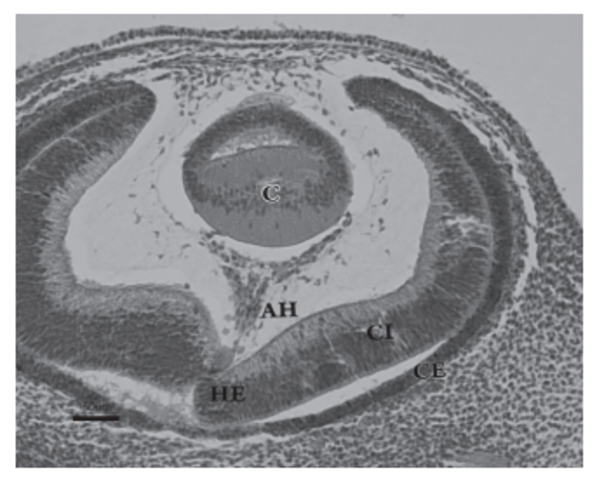

La vesícula óptica está relacionada con la formación de la placoda cristaliniana, ésta se invagina, constituyendo la vesícula cristaliniana. Al mismo tiempo, laporción distal e inferior de la vesícula óptica se deprime de forma gradual para formar una invaginación con dos capas, interna y externa, denominada cúpula óptica

Esta invaginación recorre longitudinalmente el pedículo óptico formando una hendidura conocida como hendidura embrionaria (fisura coroidea).

DESARROLLO DEL CRISTALINO

- Durante el día 32 del desarrollo, la placoda cristaliniana se invagina, hasta que un día más tarde se desprende de la superficie ectodérmica, formando la vesícula cristaliniana. Inicialmente ésta presenta una cavidad en su interior. Este fenómeno coincide con la aparición del cuerpo vítreo primario, entre la vesícula y la cúpula óptica.

Las fibras de la pared profunda de la vesícula cristaliniana se diferencian para formar las fibras primarias del cristalino, que se orientan anteroposterormente y son muy transparentes. De esta forma, se va obliterando la cavidad de la vesícula cristaliniana, hecho que ocurre al final de la séptima semana del desarrollo.

- Será ahora la vesícula cristaliniana la que induce la transformación del ectodermo de superficie dando lugar a la córnea, pero en su desarrollo también participarán células de otros orígenes. Así, el epitelio externo corneal es derivado del ectodermo de superficie, además las células derivadas de la cresta neural situadas alrededor de la cúpula óptica emigran y darán lugar al endotelio corneal.

DESARROLLO DEL IRIS Y CUERPO

CILIAR

-El iris se forma a partir del reborde de la cúpula óptica,

cubriendo parcialmente al cristalino. El epitelio iridiano

presenta las dos capas de la cúpula óptica; se continúa con el epitelio del cuerpo ciliar y con el epitelio

retiniano pigmentario y sensorial.

DESARROLLO DEL CUERPO VÍTREO

- El mesénquima que rodea la vesícula óptica penetra en el interior de la cúpula óptica a través de la hendidura embrionaria y forma el vítreo primario, que se sitúa entre la retina y el cristalino, y que consta de células mesenquimales, fibrillas producidas por la superficie interna de la retina sensorial y la cara posterior del cristalino, y vasos sanguíneos. Es rico en ácido hialurónico y glicosamina.